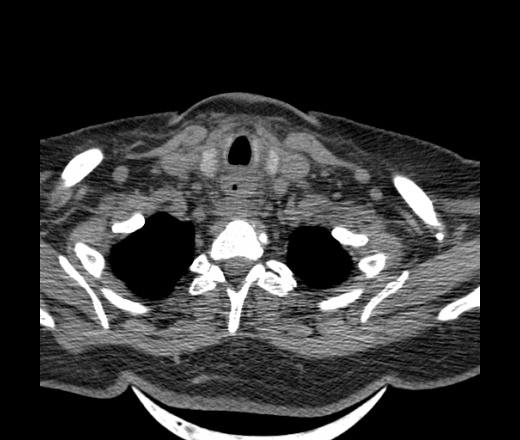

Женщина поступила в х/о спустя 4 дня после того как при употреблении карася подавилась костью.

Наличие газа в средостении на протяжении тел С2-С6 (медиастинальна эмфизема); рыбная кость на уровне тела С6.

При всем уважении, но говорить о медиастинальной эмфиземе, оценивая мягкие ткани шеи, как-то слишком резко. На мой взгляд, это ретрофарингеальное пространство.

Эвакуировали почти 100мл гноя. Но кость не смогли найти. Думаю что она даст дальнейшее ослоднение. Эндоскопически за черпалонадгортаной звязкой не смогли зайти в пищевод, все мягкие ткани отечные, просвет пищевода сдавлен. По всей видимости параэзофагеальная клетчака тоже задействована. Эмпиема, если ее можно так назвать, незнаю как правильно дошла до уровня яремной вырезки. Чем закончиться напишу. Ждем медиастинита.

Флегмона заглоточного пространства шеи, только операция, флегмоны вскрывают. Риск медиастинита.

Согласен с Вами; конечно, наличие газа в клетчатке ретрофарингеального пространства (затмение с опечаткой..). К сожалению, процесс "продвигается" к медиастиниту. Но почему никто, не отмечает наличие рыб. кости; или это для Всех очевидно?

Кость то мы сразу выявили, размеры где то 17*2мм, но ее так и не получается найти в этой каше